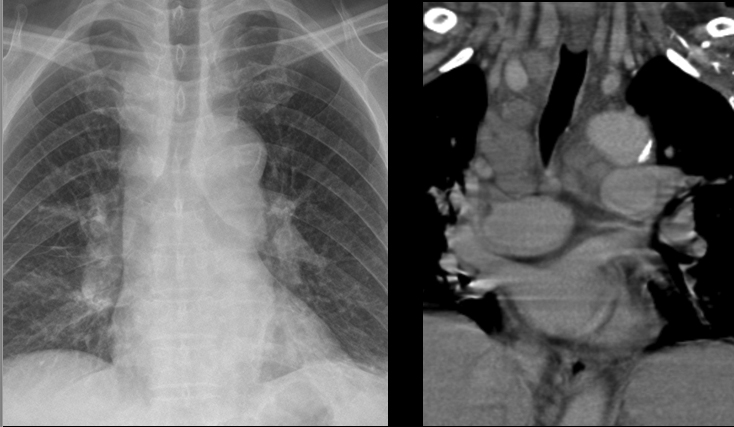

Mediastinal adenopathy